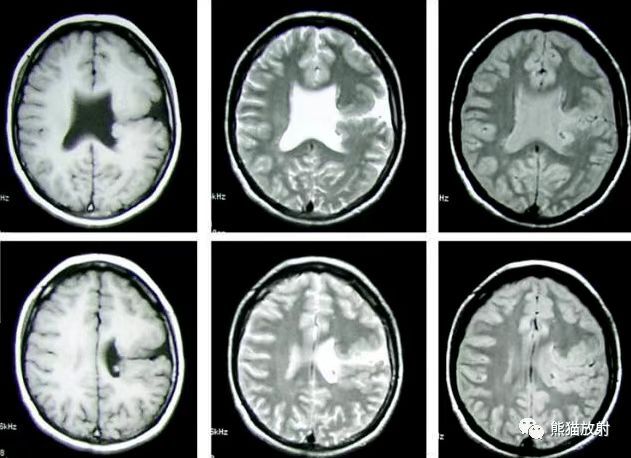

(五)CT扫描 能直观地显示脑穿通畸形的存在及类型,对了解囊肿的大小、部位、形态、数目及治疗方案选择、预后估计、鉴别诊断等均有重要意义。CT表现脑内囊肿性病变,CT值与脑脊液相似,病灶部位低密度影,与脑室相通。其他表现有脑积水、脑皮层萎缩等。强化扫描不增强。

(六)核磁共振(MRI) 呈长T1和长T2象,常与脑脊液一样,在T1加权象上呈囊状低信号,在T2加权象上呈高信号。